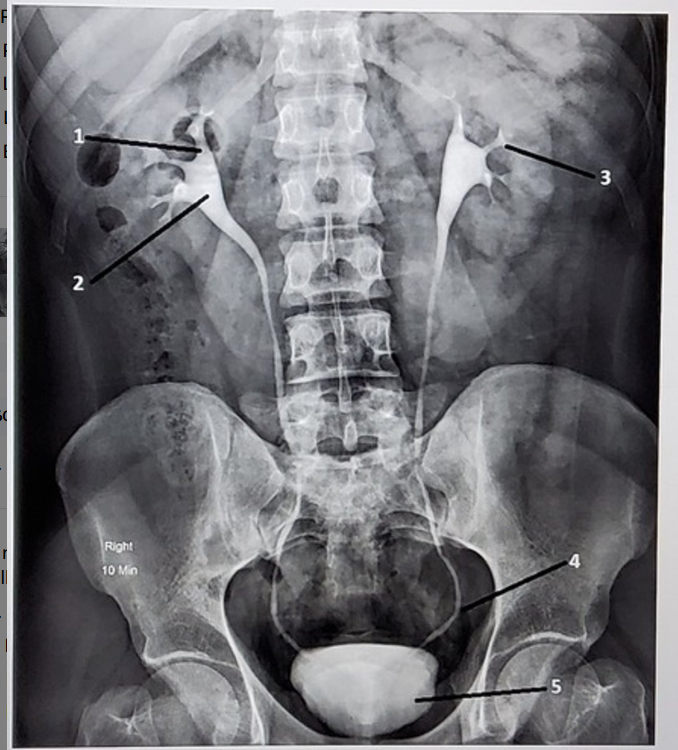

Identify the structures

1. Right major calyx

2. Right renal pelvis

3. Left minor calyx

4. Left distal ureter

5. Bladder

Identify the anatomic structures labeled on this image. Your label should be descriptive (proximal/distal, which side of the body, etc)